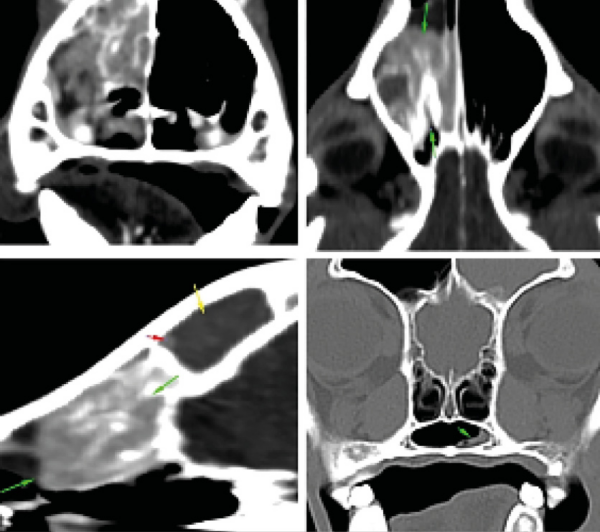

Los tumores nasales representan aproximadamente el 1 % del total de las neoplasias en la especie canina, y el adenocarcinoma es el tipo más prevalente en esta localización. La TC es una herramienta diagnóstica fundamental para la estadificación clínica y la planificación del tratamiento (imagen 23). En este contexto, la radioterapia de megavoltaje se considera la modalidad terapéutica de elección para el manejo de estos tumores.

La electroquimioterapia se presenta como una alternativa terapéutica a la radioterapia para el tratamiento de tumores localizados en la región rostral de la cavidad nasal, siempre que no exista invasión retroorbitaria ni compromiso de la lámina cribiforme o de la nasofaringe. Bajo estos criterios de selección, se han reportado tasas de respuesta objetiva del 91 %, con una mediana de supervivencia de 13,6 meses.

Para la aplicación de la electroquimioterapia en tumores nasales, es necesario el uso de electrodos diseñados específicamente para la cavidad nasal. Se recomienda el tratamiento de ambas cavidades nasales, incluso cuando la afectación se limita a un solo lado, con el fin de maximizar el control local. En tumores localizados en regiones más caudales de la cavidad nasal, la electroquimioterapia puede combinarse con cirugía mediante la realización de una rinotomía dorsal, lo que permite la aplicación directa del tratamiento sobre el lecho tumoral (imágenes 24 y 25).